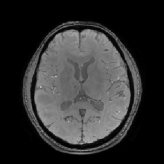

3.2 Experiments on In Vivo MR Data

The in vivo MR data experiments are conducted using 256×256×146256256146256\times 256\times 146 image with spatial resolution 0.9375×0.9375×1mm30.93750.93751msuperscriptm30.9375\times 0.9375\times 1\mathrm{mm}^{3} which can be downloaded on Cornell MRI Research Lab webpage. Using the wrapped phase image presented in Figs. 12c and 13c, we unwrap the phase using the method in [21] to obtain the total field b𝑏b in Figs. 12d and 13d Then the measured local field data blsubscript𝑏𝑙b_{l} in Figs. 12e and 13e is obtained by solving the Poisson’s equation Eq. 2.12 using the method in [57].

Figs. 14 and 15 display the visual comparisons of the direct approaches and the wavelet frame regularization approaches, and the zoom-in views of Fig. 14 are provided in Fig. 16. We also provide the visual comparisons of the direct approaches and the TGV regularization approaches in Figs. 17, 18 and 19. Since the reference image is not available for in vivo MR data, it is in general more difficult to provide quantitative evaluations than the numerical brain phantom. Nonetheless, we can see from the viewpoint of visual comparison that the pros and cons are almost the same as the numerical brain phantom experiments. It is also worth noting that the HIRE models can reduce the streaking artifacts which propagate from ΩΩ\partial\Omega into ΩΩ\Omega as well as the shadow artifacts. As pointed out in [52], the in vivo local field data is prone to the outliers near ΩΩ\partial\Omega because the GRE signal lacks information outside ΩΩ\Omega. Hence, we can see that most streaking artifacts propagate from these outliers near ΩΩ\partial\Omega into the ROI. However, thanks to the sparsity promoting property of 1subscript1\ell_{1} norm, the term λv1𝜆subscriptnorm𝑣1\lambda\left\|{\mathscr{L}}v\right\|_{1} in the HIRE approaches can somehow capture and remove them, leading to the suppression of artifacts propagating from ΩΩ\partial\Omega into ΩΩ\Omega as well as the shadow and streaking artifact removal. Finally, even though we can also note that the Tikhonov regularization can somehow reduce the artifacts, there are some losses of features due to the smoothness prior of the susceptibility image.